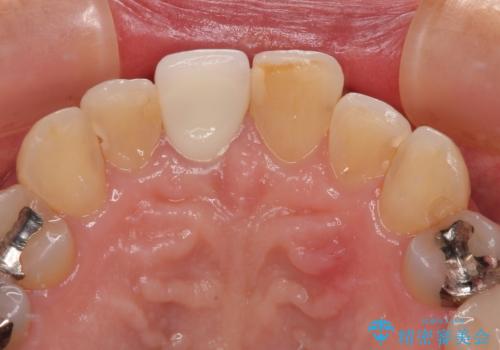

- 保険診療で装着した前歯のクラウンが変色して気になってきたとのことで来院された患者様です。

歯肉退縮による歯肉ラインの黒い縁も気になってきたとのことで、オールセラミッククラウンにて補綴治療を行うこととしました。

色がやや白いように感じますが、周りの歯をホワイトニングして白くしていくとのことで、明るめの状態での仕上がりとなりました。